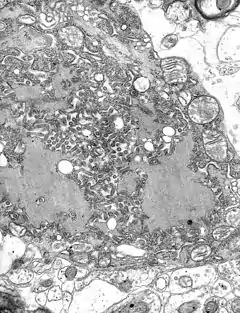

![]() TEM micrograph with numerous rabies virions (small dark-grey rod-like particles) and Negri bodies (the larger pathognomonic cellular inclusions of rabies infection) | ||||||||||

Всі транскрипції і реплікації подій відбуваються в цитоплазмі всередині тільця Негрі (названий на честь Адельчі Негрі [3]). Діаметр становить 2-10 мкм і є типовим збудником сказу і, таким чином, був використаний як певний гістологічний доказ існування такої інфекції [4].